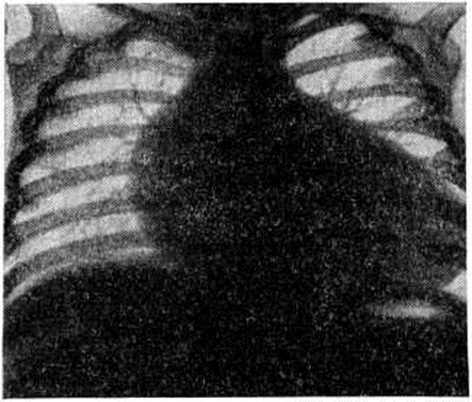

При рентгенологическое исследовании выявляется нормальный или несколько усиленный но венозному руслу лёгочный рисунок, кардиомегалия, шаровидная или овоидная форма сердца (рисунок). Пульсация снижена. Кардиоторакальный индекс — отношение поперечного размера сердца к поперечному размеру грудной клетки на уровне диафрагмы, выраженное в процентах,— составляет у большинства больных 70—75% (в норме у детей 50%). На ЭКГ (смотри полный свод знаний: Электрокардиография) — нормальное положение электрической оси сердца, высокий вольтаж зубцов, ригидный частый ритм, признаки гипертрофии миокарда левого предсердия и желудочка, глубокие отрицательные или сглаженные зубцы Т в отведениях V4-6, опущение сегмента S Т ниже изолинии. Нарушения ритма и проводимости не характерны для Фиброэластоз субэндокардиальный, однако возможно появление экстр асистолии (смотри полный свод знаний), пароксизмальной тахикардии (смотри полный свод знаний), внутрижелудочковой и атриовентрикулярной блокад (смотри полный свод знаний: Блокада сердца). При фонокардиографическом исследовании (смотри полный свод знаний: Фонокардиография) выявляется значительное снижение амплитуды I тона и систолический шум лентовидной формы в области верхушки сердца.

Рис | ||